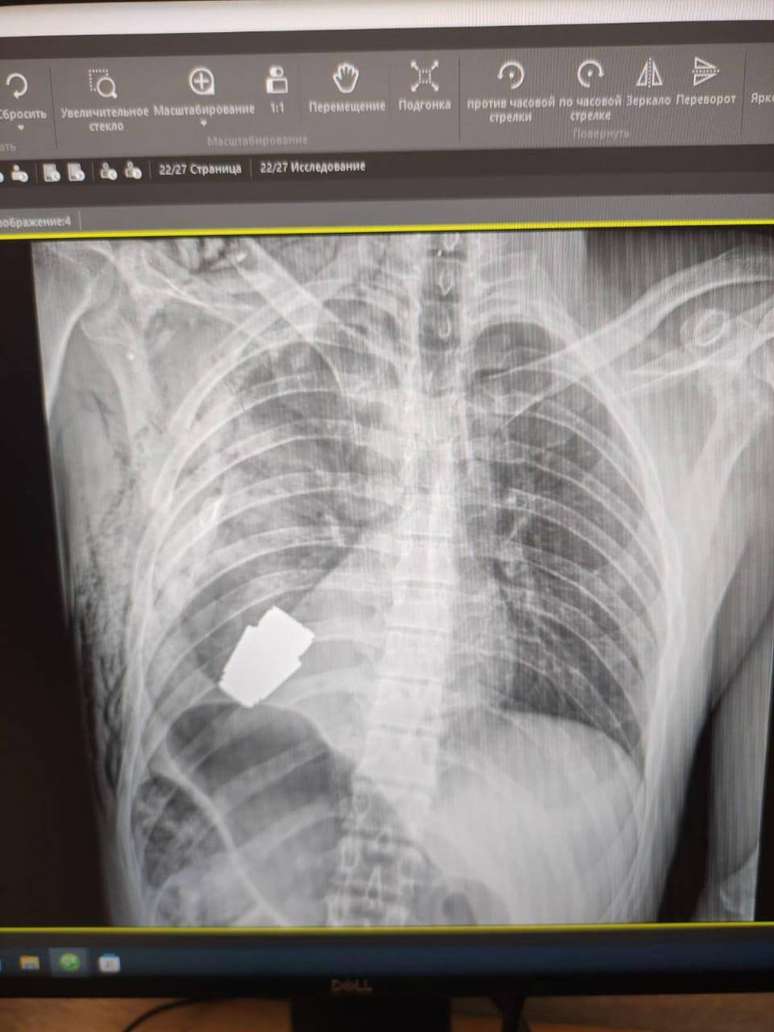

Um raio-x mostra o quão perto a granada chegou ao coração do soldado

Foto: Hanna Maliar Facebook / BBC News Brasil